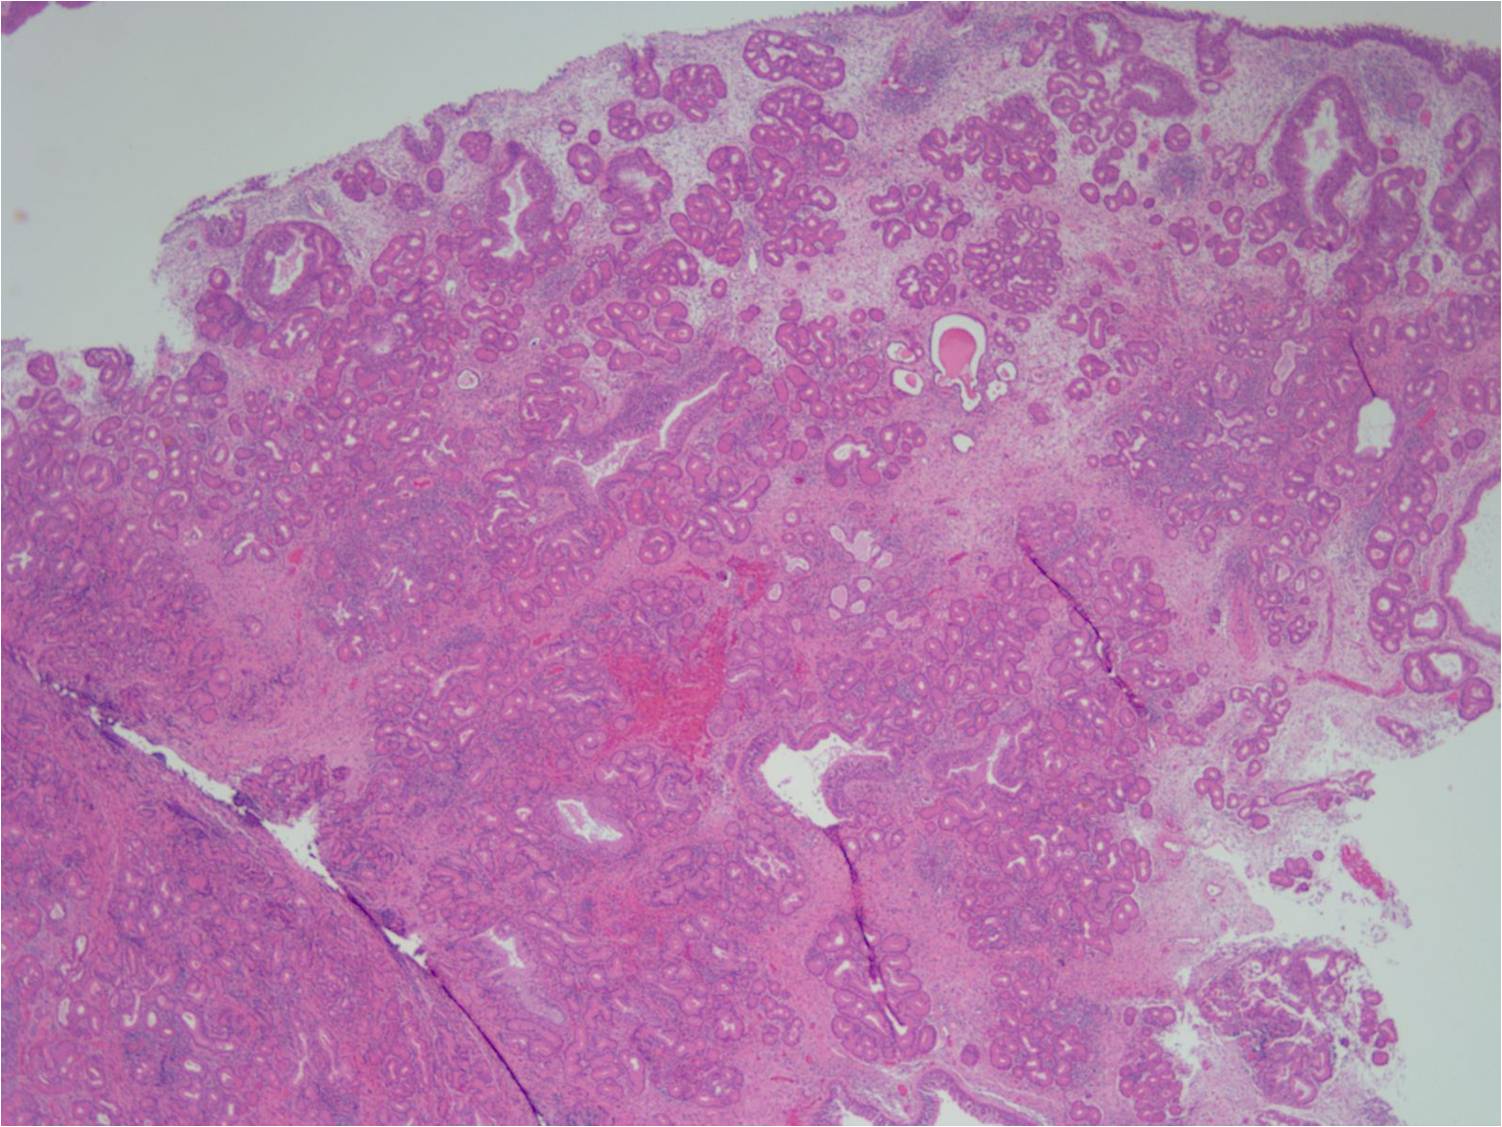

Исследование: микропрепарат молочной железы в медицине

Раздел: Снимки-откровения